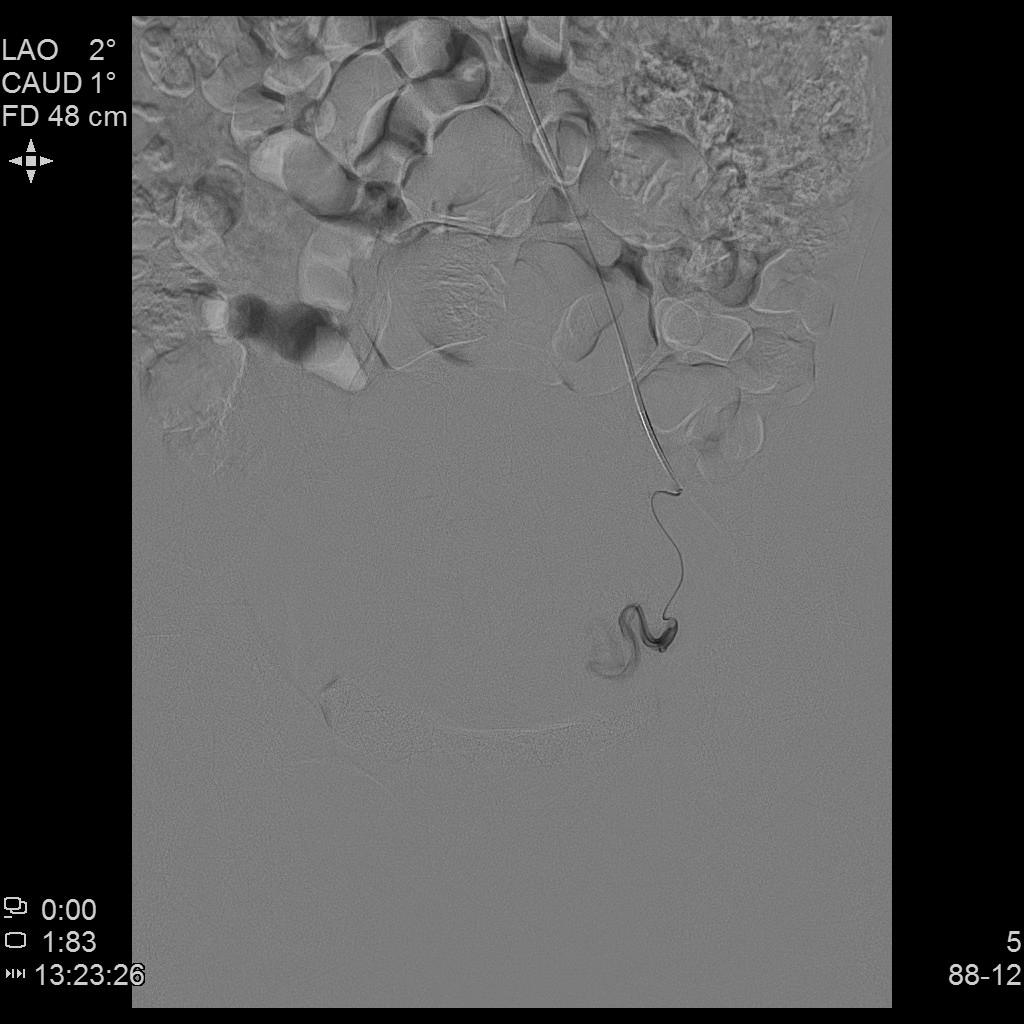

- 插管至右侧子宫动脉,显示子宫右侧病灶情况

- 插管至左侧子宫动脉,显示子宫左侧病灶情况

右侧子宫动脉造影

左侧子宫动脉造影

左侧子宫造影